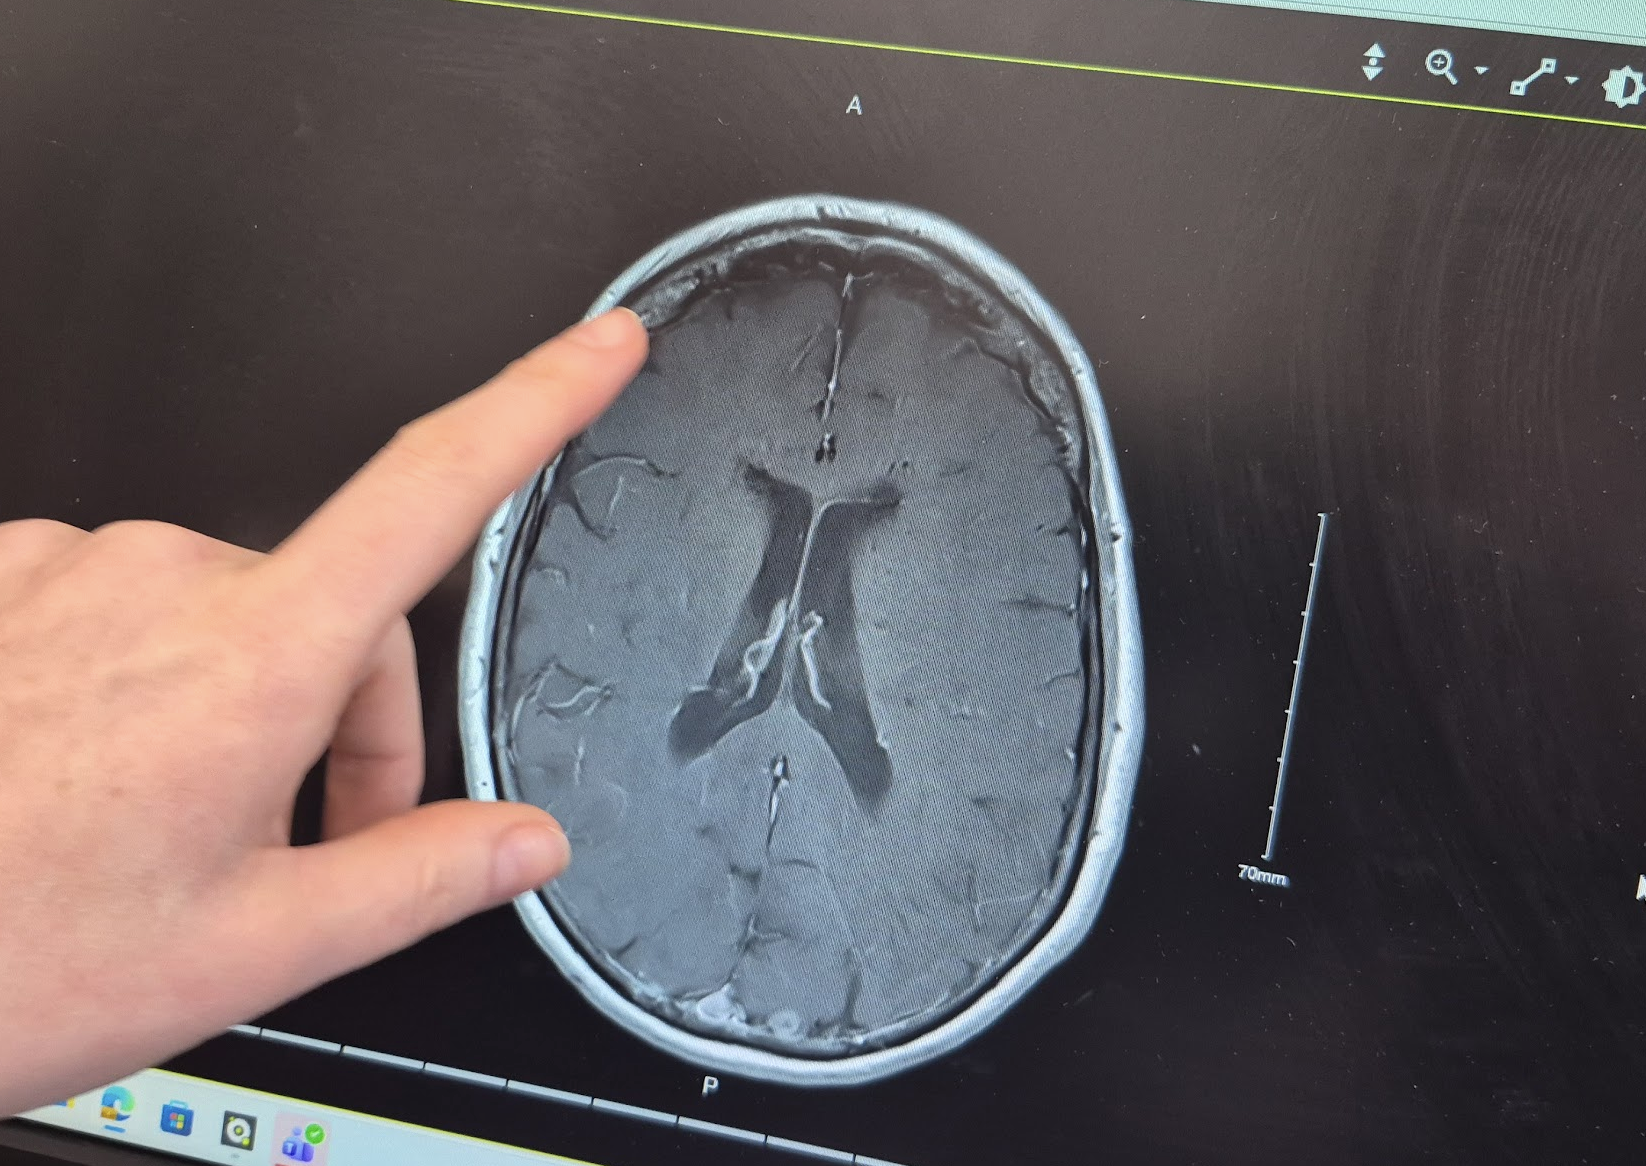

Then, though, something of more interest came up. “Over here, though,” Doctor Amy said, “we found this…”

It’s a 1.5cm meningioma in the left temporal lobe—a tumor of the meninges, one of the “containers” of tissue that hold the brain inside them.

Even from this not terribly tightly-focused imaging, it was apparently immediately clear to the radiologist reading the brain-scan MRI that the meningioma was NOT at this point dangerous. As more detailed diagnosis of such a problem isn’t in their specific specialty area, RVEEH will be forwarding this imaging to their colleagues at the neurology end of Beaumont Hospital in Dublin for further evaluation; and they (if they think it’s necessary) will pull me in for more imaging and an evaluation of what further action, if any, should be taken.